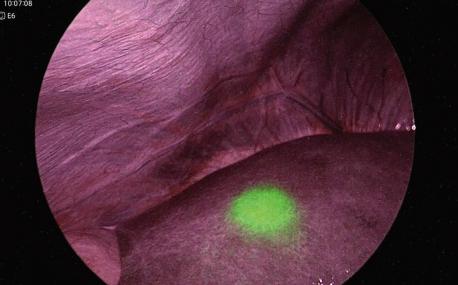

我院新购置一台日本奥林巴斯全高清荧光腹腔镜,设备见下图:

该腹腔镜除具备其他高清腹腔镜优势的同时,具有IR荧光功能,荧光光源发出白光和波长805 nm的近红外激发光,照射到观察组织时, 观察组织与ICG的结合物发出835 nm的近红外反射光,该反射光可被特殊的摄像系统实时扑捉,即可在摄像屏幕上呈现荧光视频图像:

荧光信息(绿色) 荧光部分组织形态(凹凸感)及血管走向等细节丰富呈现

背景信息(紫红色) 与荧光图像形成高对比度并且背景视野清晰明亮

提高对微小组织的识别,能够更加准确的捕捉病变部位,为患者保驾护航。